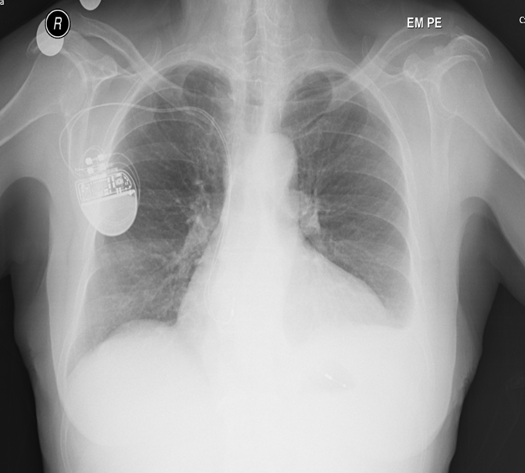

Thymic epithelial tumours represent a heterogeneous group of rare thoracic cancers. In adults, thymomas are the most common neoplasms arising in the thymus which is located in the anterior mediastinum. Mediastinal mass can be incidental findings on chest x-ray or present with systemic symptoms and/or direct effect of the mediastinal mass. The authors present the case of a 65-year woman with iron deficiency anaemia, hepatosplenomegaly, paravertebral node and mediastinal mass. Biopsy of the paravertebral node revealed extramedullary hematopoiesis (EMH). Biopsy of mediastinal mass revealed thymoma. She underwent video-assisted thoracoscopic surgery (VATS) thymectomy. The lesion was classified by the World Health Organization (WHO) system type B2 thymoma staging system of the tumor, node, metastasis (TNM) pT1a R0, Masaoka-Koga stage II. Three months later, thoracic computed tomography (CT) revealed a nodule inferior to the tumor site suspected of residual disease. The unexpected residual thymoma required treatment with radiotherapy. This case illustrates the difficulty of differentiating the etiology of anaemia. It highlights the current diagnostic approach to mediastinal mass.